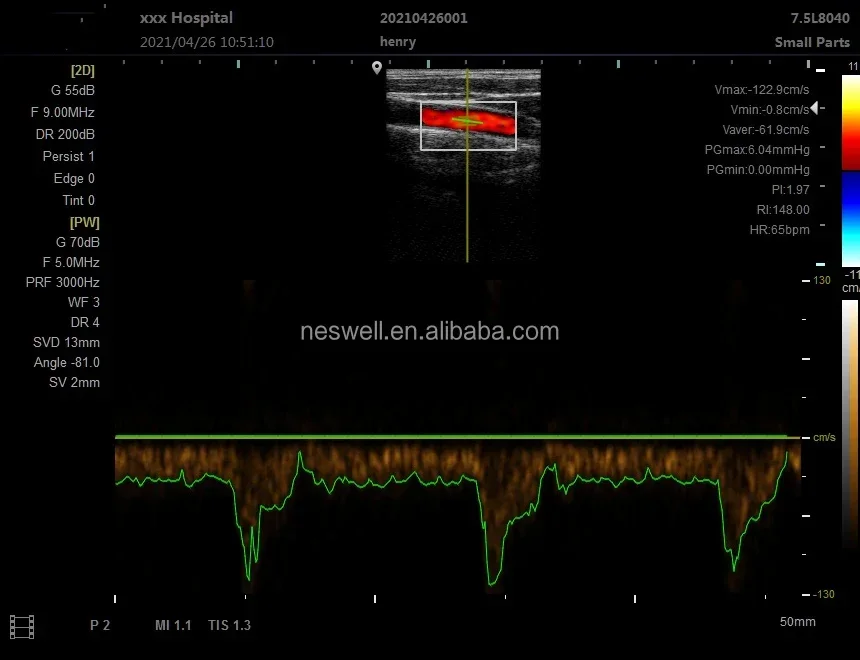

Linear Probe Parameters

-Scanning mode: Electronic array

-Display mode: B, B/M

-Frequency: 7.5MHz/10MH

-Scan depth: 20/40/60/100mm

-Image Adjust: BGain, TGC, DYN, Focus, Depth, Harmonic, Denoise, Color Gain, Steer, PRF

-Cineplay: auto and manual, frames can set as 100/200/500/1000

-Puncture assist function: the function of in-plane puncture guide line, out-of-plane puncture guide line, automatic blood vessel measurement.

-Measure: Length, Area, Angle, heart rate, Obstetrics

-Image save: jpg, avi and DICOM format

-Image frame rate: 18 frames / second

Linear Probe Pictures: